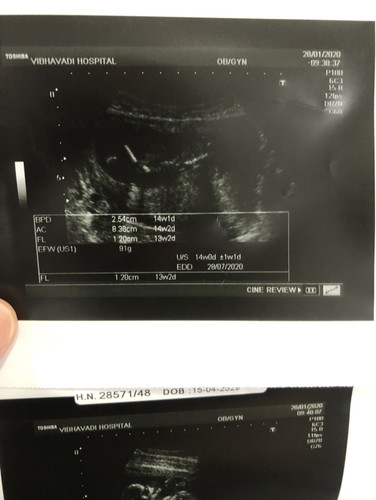

13 wk 5 วัน น้ำหนักลูกประมานเท่าไหร่กันเเล้วค่ะ

13wk 5 วัน หมอวัดได้น้ำหนักลูกประมาน 91 กรัมเเล้วค่ะ